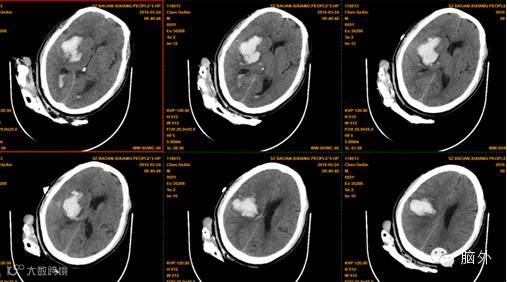

患者陈**,男,55岁,因“突发左侧肢体乏力伴言语不清1小时”于2016年3月23日拟“1.脑出血”收入本区。入院示头颅CT提示:右侧基底节、外囊、丘脑、放射冠区脑出血。出血量约40ml。完善相关术前准备后,在全麻下为患者施行了完全神经内镜下脑内血肿清除术,术程顺利,整过手术过程出血仅数毫升,术后患者清醒,正在康复中。

术前CT: